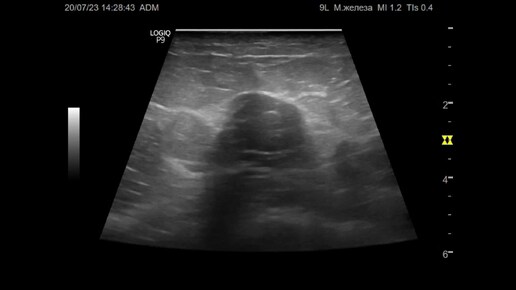

Ультразвуковая диагностика (УЗИ). Доктор Иогансен. Видеопримеры. Выпуск 100. Рак молочной железы (4).